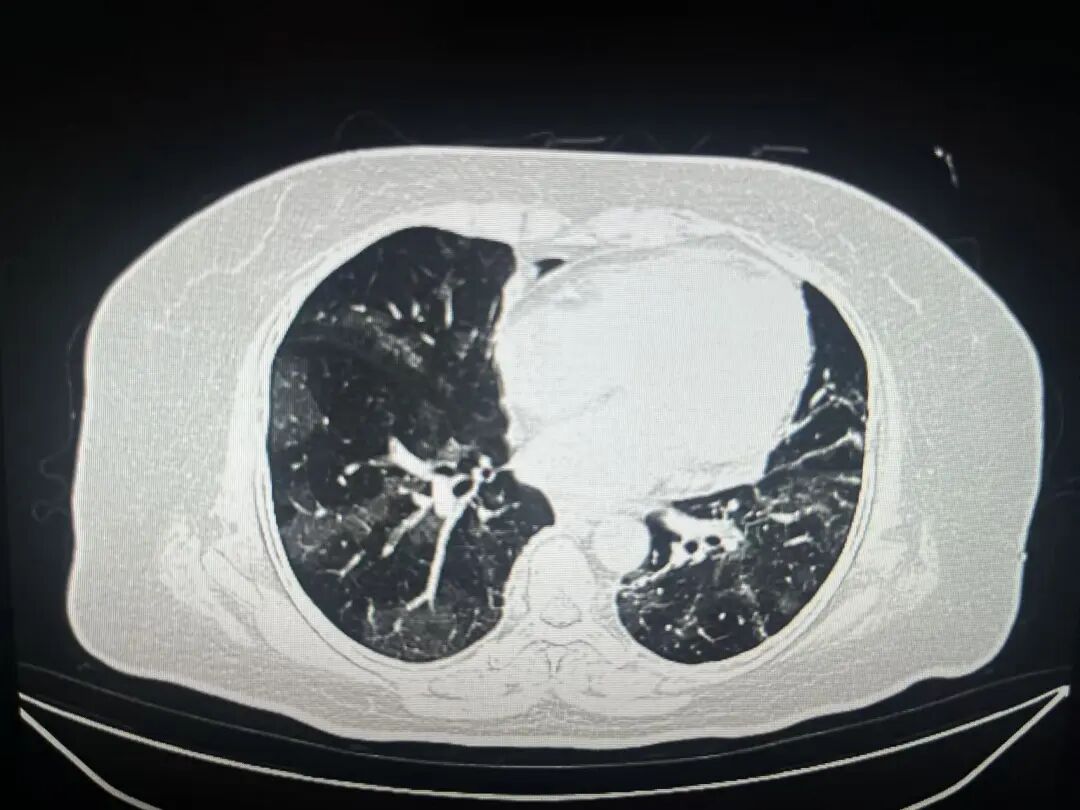

病毒性肺炎的典型CT特征

磨玻璃影——最早期的信號

● 表現(xiàn):像一片薄霧籠罩在肺野上,血管紋理仍可辨認(rèn)。

● 意義:代表早期炎癥細(xì)胞浸潤和肺泡壁增厚。

● 分布:多位于肺外周、胸膜下區(qū)域。

2

鋪路石征——疾病進(jìn)展標(biāo)志

● 表現(xiàn):磨玻璃背景上出現(xiàn)小葉間隔增厚,如同不規(guī)則鋪路石。

● 意義:炎癥加重,淋巴管受累。

多灶性、雙側(cè)性分布

● 病毒性肺炎常同時累及多個肺葉,雙側(cè)分布。

● 這與某些細(xì)菌性肺炎的局灶性分布形成對比。

新冠病毒肺炎

● 典型分布:胸膜下、雙側(cè)多發(fā)磨玻璃影。

● 進(jìn)展特點(diǎn):可快速融合,出現(xiàn)“白肺”表現(xiàn)。